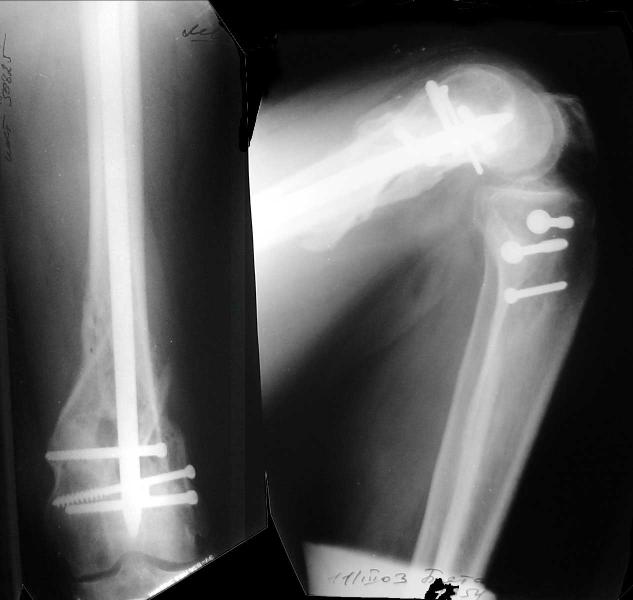

Look what we would have done.

I would not say that the LISS is superior to the nail. If I would, I had not post original mail. I wanted to generate discussion. Your option is a very viable one. I feel a little bit shaky the distal femur, but it is just gut feeling no science behind it. Any way nice fixation, congarts!

I presented the series at EuroTrauma in May. The "Distal Femur" section of the meeting was very interesting.